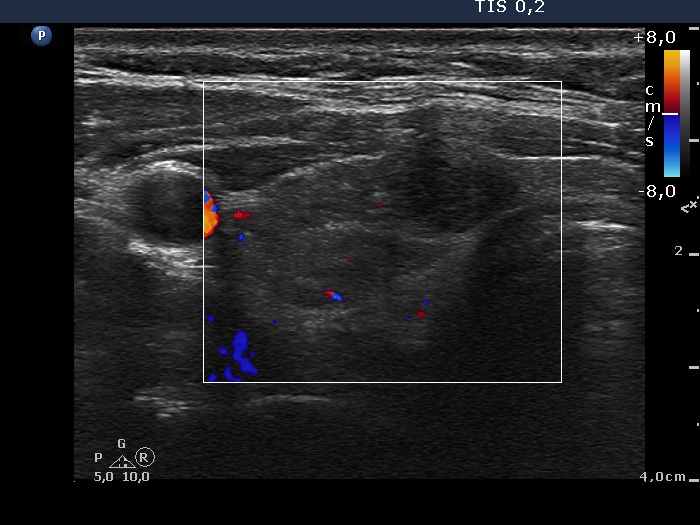

Patient referred for evaluation of thyroid nodule - final diagnosis Hashimoto's thyroiditis - Case 1. (ultrasonographic picture 3)

Right lobe, horizontal view, color Doppler mode. The lesion is avascular.